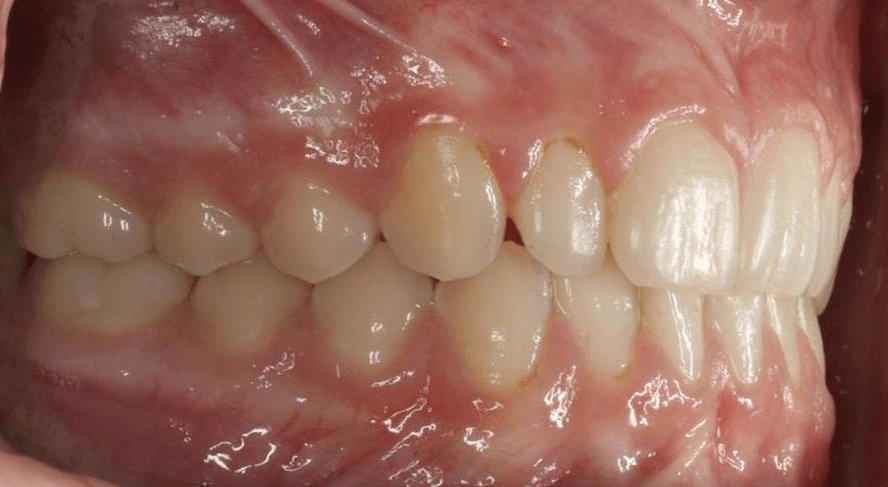

Initial treatment

INTRAORAL